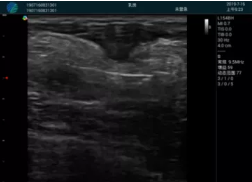

可視化甲狀腺穿刺引導(dǎo)

頸動(dòng)脈血流充盈飽滿,無外溢